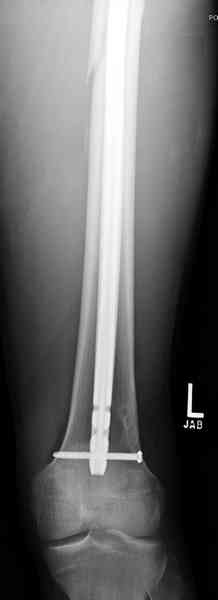

В приложении пример огнестрельного ранения бедра, оперированного на 2 сутки после ранения.

Штифтование было выполнено только на вторые сутки по причине задержки перевода из другого госпиталя, АБ профилактика была начата в другом учреждении, с момента госпитализации пациента к ним. Входное пулевое отверстие и зона введения штифта зажили первичным натяжением.

Единственно что наблюдал - замедленная консолидация, судя по серийным Рг граммам. В приведенном случае прии вялом мозолееобразовании сделал ошибку, решившись динамизировать гвоздь - перелом сросся со значительным укорочением бедра - повторная хирургия по удлинению бедра и проксимальным запиранием, больной мобилизован и вполне доволен(кстати заметить больной с ВИЧ инфекцией - изначально скомпрометированный иммунитет и несмотря на это, всё прошло без костной и мягкотканной инфекции.